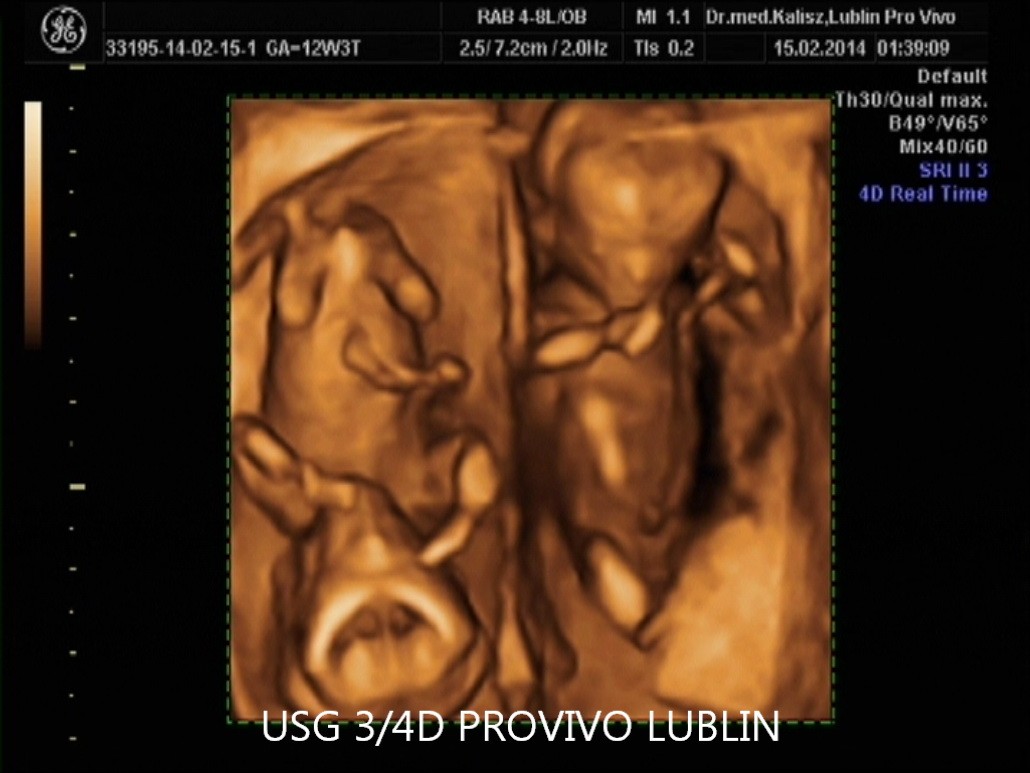

USG 4D pokazuje obraz podobny do badania 3D, ale dodatkowo rejestruje go w czasie rzeczywistym. Oznacza to, że rodzice mogą obserwować ruchy dziecka, mimikę twarzy i zachowanie płodu niemal jak podczas podglądu na żywo.

Dla wielu przyszłych rodziców jest to niezwykle ważny i wzruszający moment, ponieważ po raz pierwszy mogą zobaczyć swoje dziecko w ruchu jeszcze przed narodzinami. Aktualna treść strony PROVIVO również podkreśla ten emocjonalny wymiar badania 4D.

Na stronie PROVIVO wskazano, że badanie może być wykonane między 11. a 14. tygodniem ciąży, a następnie około 20. lub 30. tygodnia ciąży. To właśnie w tych okresach można uzyskać wartościowe obrazy płodu i lepiej ocenić jego rozwój.